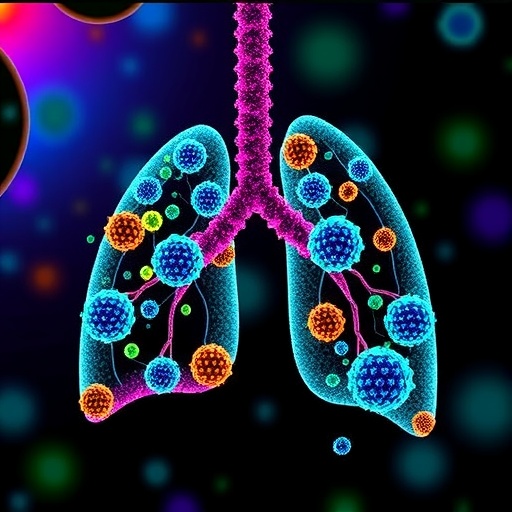

(Vall d'Hebron Institute of Oncology) Researchers at the Vall d'Hebron Institute of Oncology in Barcelona show that the p95HER2-T cell bispecific antibody (TCB) can successfully guide immune cells, known as lymphocytes, directly to cancerous ones for their targeted killing. This direct delivery is achieved thanks to the p95HER2 protein, which is only located in tumor cells.

T cell bispecific antibody for the immune-mediated killing of HER2+ breast cancer cells